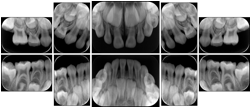

Intra-oral radiography typically involves acquisition of multiple images of various parts of the dentition. Many digital radiographic systems offer customized templates that are used for displaying the images in a study on the screen. These templates may also be referred to as mounts or view sets. The Structured Display Object represents a standard method of encoding and exchanging the layout and intended display of Structured Displays. A structured display object created in this manner could be stored with a study and exchanged with images to allow for complete reproduction of the original exam.

1. A patient visits a General Dentist where a Full Mouth Series Exam with 18 images is acquired. The dentist observes severe bone loss and refers the patient to a Periodontist. The 18 images from the Full Mouth Series along with a Structured Display are copied to a DICOM Interchange CD and sent with the patient to see the specialist. The Periodontist uses the CD to open the exam in his Dental Radiographic Software and consults via phone with the General Dentist. Both are able to observe the same exam showing the images on each user's display using the exact same layout.

Intra-oral Full Mouth Series Structured Display

Figure OO-1. Intra-oral Full Mouth Series Structured Display